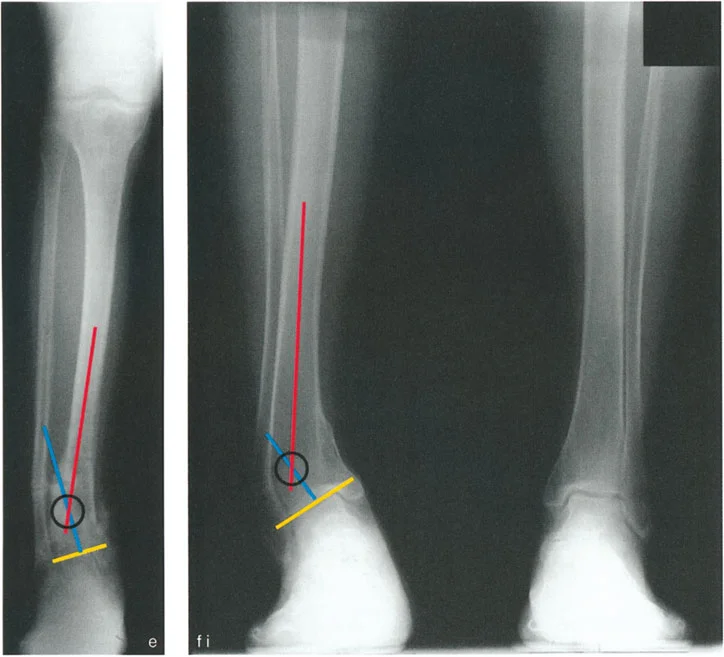

* رسم المحاور الميكانيكية والتشريحية: لتحديد نقطة مركز دوران التشوه (CORA)، وهي النقطة التي يجب أن تتم عندها الجراحة لتصحيح التشوه بأقل قدر من المضاعفات.

تُعد مبادئ الدكتور درور بالي حجر الزاوية في جراحة تصحيح تشوهات العظام. تركز هذه المبادئ على تحديد "مركز دوران التشوه" (CORA - Center of Rotation of Angulation) بدقة. إن موقع CORA يحدد كيفية تأثير التشوه على المفاصل المجاورة ويوجّه الجراح في اختيار مكان قطع العظم (Osteotomy).

• فهم CORA:

• إذا كان CORA قريبًا من مفصل الكاحل، فإن التشوه يؤثر بشكل أساسي على محاذاة الكاحل.

• إذا كان CORA قريبًا من مفصل الركبة، فإن التشوه يؤثر بشكل أساسي على محاذاة الركبة.

• إذا كان CORA في منتصف عظم الساق، فإنه يؤثر على كلا المفصلين ولكن بدرجة أقل.

• قواعد بالي لقطع العظم:

1. القاعدة الأولى: عندما يمر قطع العظم ومحور تصحيح الزاوية (ACA) عبر CORA، يتم تحقيق تصحيح زاوي نقي دون أي إزاحة.

2. القاعدة الثانية: عندما يمر ACA عبر CORA، ولكن قطع العظم يتم في مستوى مختلف (غالبًا ما يكون ضروريًا لتوفير مساحة كافية للتثبيت)، يتم تحقيق تصحيح زاوي نقي، ولكن أطراف العظم ستنزاح في موقع قطع العظم. يجب على الجراح توقع هذه الإزاحة وإدارتها.

3. القاعدة الثالثة: إذا كان ACA وقطع العظم في نفس المستوى، ولكن لا يمر أي منهما عبر CORA، فسيحدث تشوه إزاحة (ترجمة) غير مرغوب فيه. يتطلب هذا الأمر من الجراح إجراء إزاحة متعمدة للقطعة العظمية البعيدة أثناء التصحيح الزاوي لإعادة محاذاة المحور الميكانيكي.